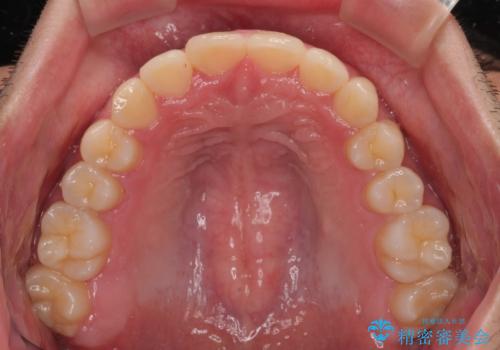

- ディープバイトと上顎前歯の突出、奥歯の咬み合わせを気にして来院された患者様です。

上顎歯列は全体的に前方位にあり、それが原因で深い咬み合わせとなり、突き上げにより上顎前歯が前方に飛び出している状態でした。

また、左右ともに上顎最後臼歯が頬側に転位している鋏状咬合となっていました。

インビザラインによる矯正治療をご希望でしたが、上顎歯列の前方位と鋏状咬合を確実に改善することを目的として、補助装置を併用することとしました。